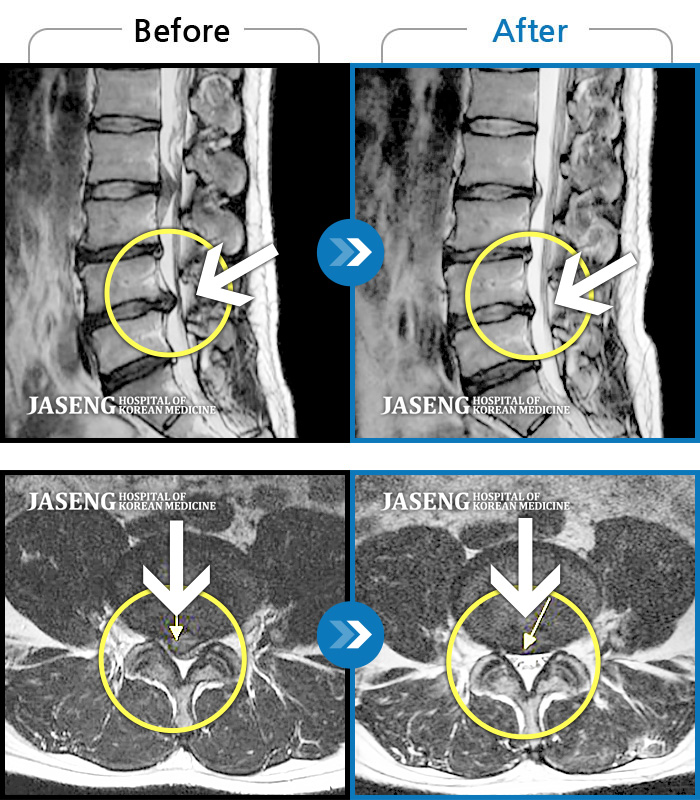

Before

After

허리 통증, 좌하지 방사통 저림

2013.10.01 ~ 2016.12.07